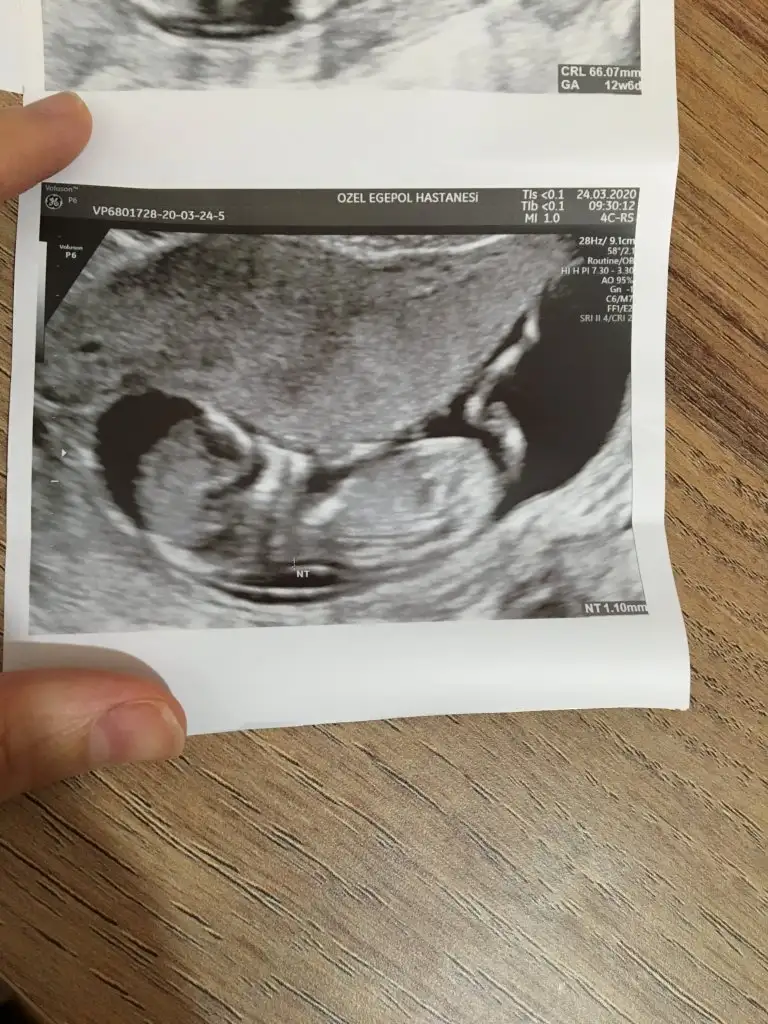

Merhaba bana da tahmin yapabilir misiniz dosya ekledim 12+6 ya ait ultrason görüntüsü

dr soylemeden siz gorun genital nub teorisi ( bebegin cinsiyeti)